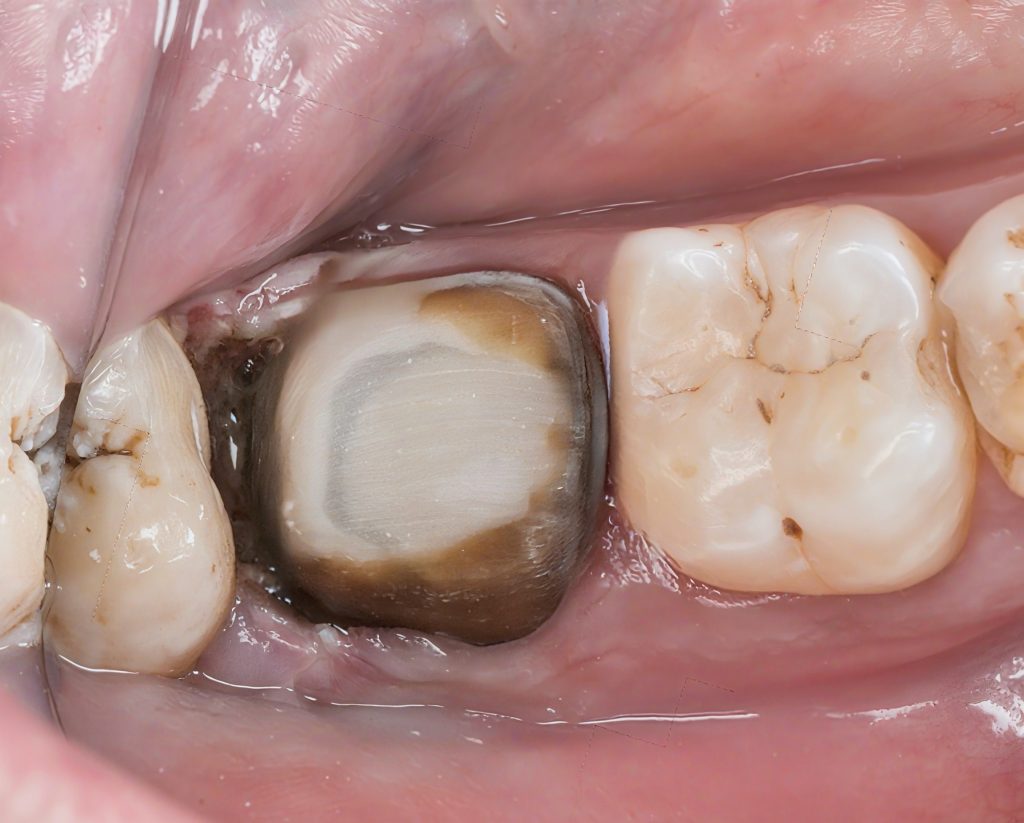

1. Pre-operative Evaluation

The tooth presented with:

- A large, deteriorated amalgam filling

- Recurrent deep caries

- Structural cracks undermining both cusps

- Radiographic involvement suggesting pulpal disease

Diagnosis:

Irreversible pulpitis with structural compromise requiring endodontics and cuspal coverage.

This combination of caries, cracks, and failing restoration made a traditional direct composite unpredictable.

A full biomimetic workflow was the only path to long-term stability.

2. Removal of Old Restoration and Caries Control

Under the microscope, the old amalgam was removed. The underlying picture revealed the true extent of disease:

- Soft, contaminated dentin

- Undermined enamel shells

- Sub-occlusal caries tracking toward the pulp

- Deep structural compromise